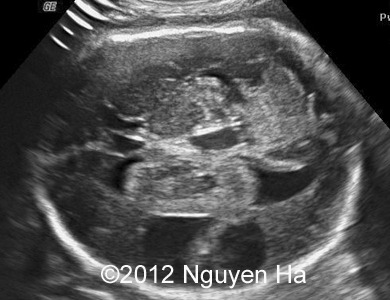

A 30-year-old woman (G1P0), with unremarkable family history, presented to our unit at 36 weeks of her pregnancy. She did not undergo any previous screening tests. Our examination (and repeated scan after four days) revealed following findings:

Figures 1-7: 36 wekks of pregnancy.

A 30-year-old woman (G1P0), with unremarkable family history, presented to our unit at 36 weeks of her pregnancy. She did not undergo any previous screening tests. Our examination revealed unilateral hypoechoic inhomogeneous mass within cerebral parenchyma. Our initial diagnosis was teratoma, but repeated exam after four days showed structural changes and different echogenicity of the mass and so our final diagnosis was cerebral hemorrhage. The findings were confirmed by MRI scan.

Figure 1-7: 36 wekks of pregnancy.